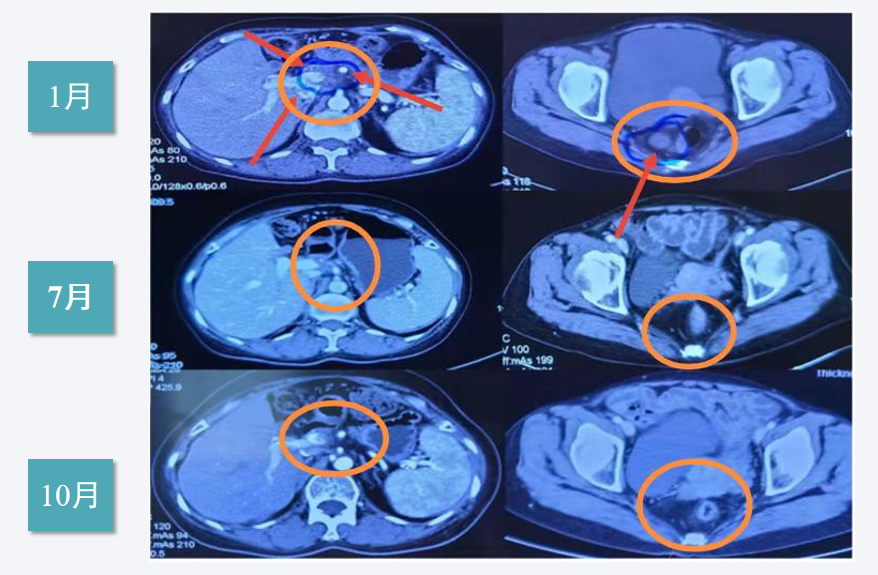

胰体部转移淋巴结CT:2周期后变化不大,4周期后调整含铂化疗方案病灶明显变小

2020年CT提示病灶迅速缩小,10月基本消失